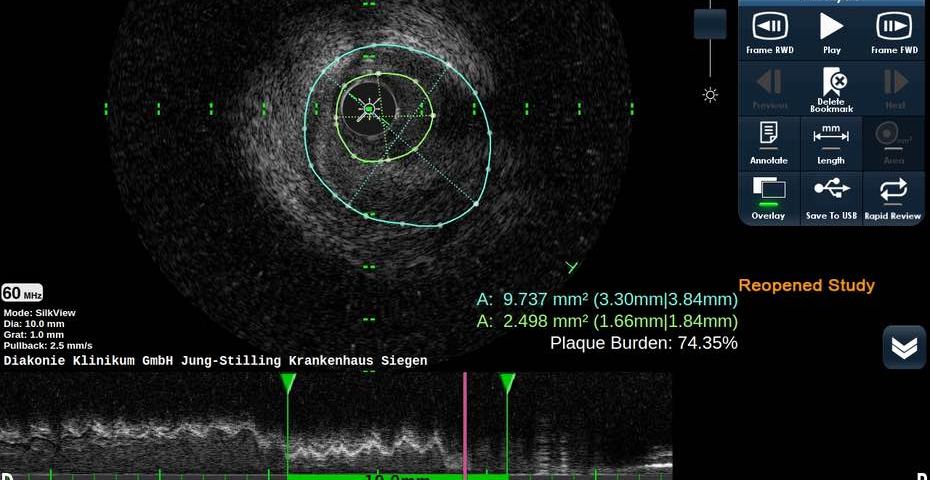

SIEGEN. Als CTO bezeichnen Fachärzte der Kardiologie chronische Koronarverschlüsse mit einer Dauer von mehr als drei Monaten. Zur Behandlung führen Kardiologen sogenannte Perkutane Koronarinterventionen zur CTO-Rekanalisation (CTO-PSI) durch. „Dabei handelt es sich um anspruchsvolle und komplexe Prozeduren, die wegen einer hohen Menge an Kontrastmitteln und Strahlung, die während der Behandlung zum Einsatz kommt, mit einer nicht unerheblichen Belastung für den Patienten einhergehen“, stellt Prof. Dr. Dursun Gündüz , Chefarzt der Kardiologie am Diakonie Klinikum Jung-Stilling in Siegen heraus. Eine neue Studie(1) unter Federführung einer Gruppe europäischer CTO-Experten nimmt deshalb die Frage in den Blick, ob aus dem hohen Aufwand für die Behandlung auch ein relevanter Nutzen für die Patienten entsteht. Erste Ergebnisse liegen jetzt vor.

Ziel der sogenannten EURO-CTO Studie ist es, CTO-PSI mit einer optimalen medikamentösen Therapie (OMT) und ihrer jeweiligen Wirkung auf den Gesundheitszustand bzw. die Lebensqualität der Patienten zu vergleichen. In den Fokus nahmen die Studienautoren dabei Einschränkungen der körperlichen Aktivität, Dauer und Häufigkeit von Angina-Pectoris, die Zufriedenheit der Patienten und ihre Krankheitswahrnehmung. In die Studie eingeschlossen wurden zunächst 407 Patienten mit einer koronaren Ein- bzw. Mehrgefäßerkrankung. 137 erhielten eine OMT, 259 darüber hinaus eine CTO-PCI.